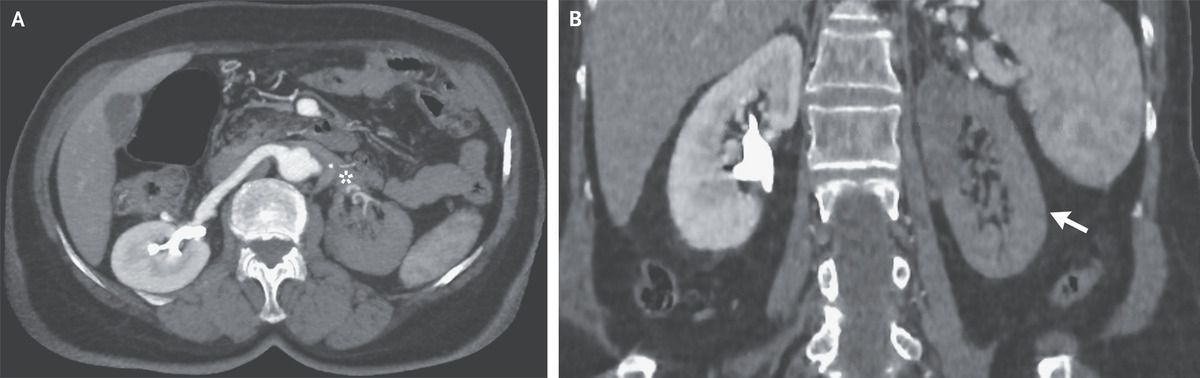

A 73-year-old woman presented to the emergency department with a 2-day history of left flank pain. She had no cardiovascular risk factors or history of tobacco use. Her body temperature was 38.5°C. Findings from a physical examination were normal. Laboratory testing was notable for a platelet count of 652,000 per cubic millimeter (reference range, 150,000 to 400,000) with an otherwise normal complete blood count. No previous platelet count was available. The lactate dehydrogenase level was 422 U per liter (reference range, 100 to 250). Computed tomography of the abdomen with intravenous contrast material showed a filling defect in the left renal artery (Panel A, asterisk) and a perfusion defect in the left renal cortex (Panel B, arrow) — findings that were consistent with an occlusive thrombosis of the left renal artery and associated renal infarction. Further testing revealed no evidence of cardioembolic disease, renal artery injury, or inherited thrombophilia. Owing to a persistently elevated platelet count, genetic testing was performed for the JAK2 V617F variant, and the result was positive. A diagnosis of essential thrombocythemia was made. Essential thrombocythemia may be complicated by arterial or venous thrombosis. The goal of treatment in patients with this condition is the prevention of vascular events. Treatment with hydroxyurea and aspirin was initiated. At follow-up 2 months later, the patient felt well and the platelet count was normal.